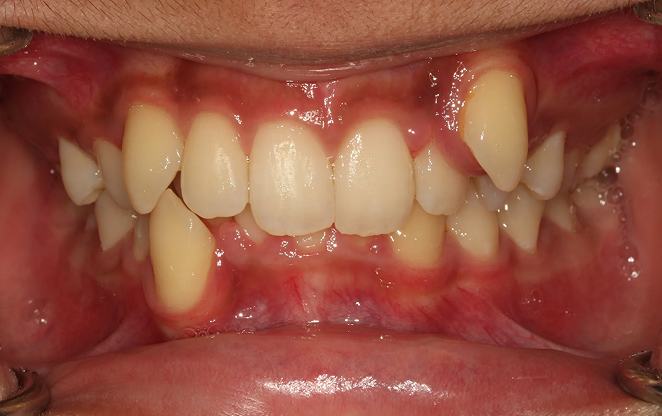

Before

After